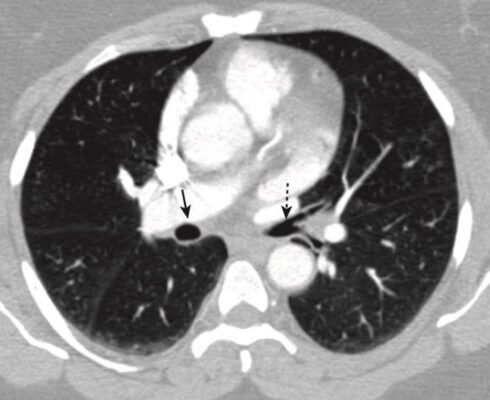

- Các phế quản và tiểu phế quản cũng có thể nhìn thấy được, và theo quy luật, các phế quản thường nhỏ hơn các động mạch phổi đi kèm (Hình 13).

- Thấp hơn một chút là phế quản chính phải và trái và các phế quản trung gian. Phế quản chính bên phải có hình dạng một cấu trúc hình tròn, chứa khí và sẽ trở thành hình ống khi phế quản thùy trên bên phải xuất hiện. Sau phế quản trung gian không có gì ngoài mô phổi (Hình 15).